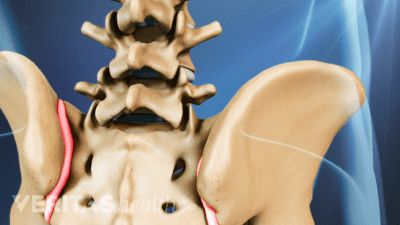

Learn about the differences between sacroiliitis and arthritis. It’s important to note that sacroiliitis is linked to inflammatory arthritis but can occur independently.